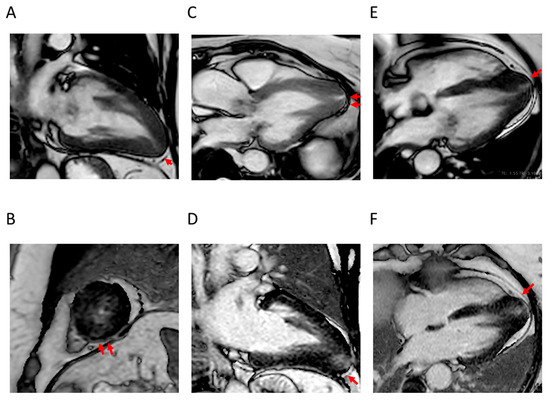

4.2. Apical Aneurysm

4.3. LVOTO

4.4. LV Function